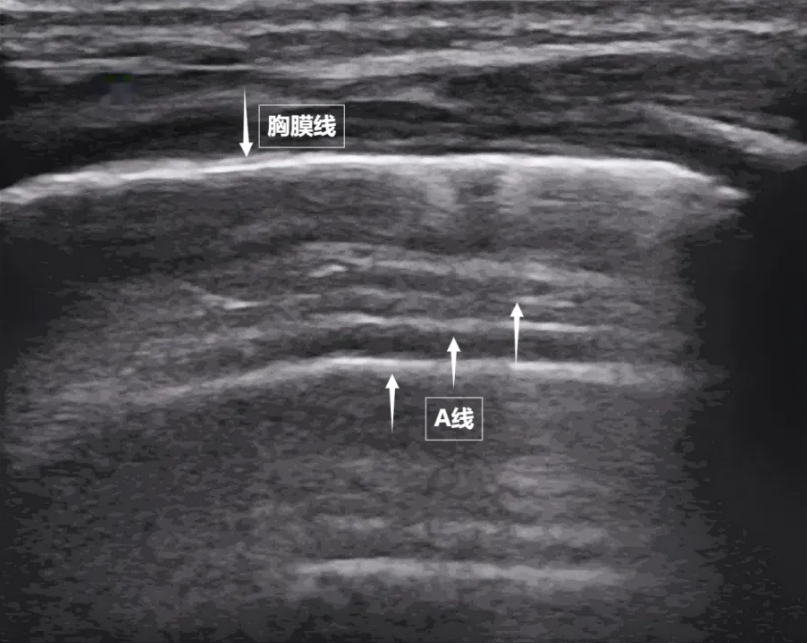

第一景:“海岸线与海浪”——胸膜线与A线当声波穿过胸壁肋骨缝隙,首先会遇到紧贴肺表面的光滑薄膜——壁层胸膜和脏层胸膜。两者紧密相贴,中间没有多余的气体或液体。它们在屏幕上呈现为一条明亮、光滑的水平线,共同构成了胸膜线。这条线就是肺的“海岸线”。在它的下方,由于肺泡内大量气体对声波的强烈反射,会出现一系列与胸膜线平行的、等间距的、重复出现的明亮平行线,像海浪般不断向屏幕深处延伸,这就是A线(见下图)。A线是正常含气肺部的典型标志。它的存在直接提示肺表面含气充足,胸膜腔内无异常积液或气体。

图为正常新生儿肺部超声表现